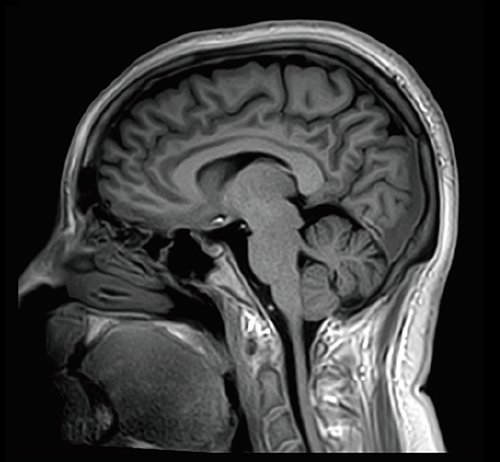

KI-optimiertes Arbeiten und modernste 3T-Technologie machen den Vantage Galan 3T von Canon Medical aus. Canons KI-Anwendung AiCE, kurz für Advanced intelligent Clear-Imagequality Engine, entfernt intelligent das Rauschen und führt zu einer Verbesserung des SNR (Signal-Rausch-Verhältnis). Mit Hilfe der Deep Learning Technologie gelingen besonders klare und deutliche Bilder. Insgesamt ermöglicht die KI-Unterstützung des Vantage Galan 3T somit nicht nur eine höhere Auflösung der Bilder, sondern verkürzt in vielen Fällen auch die Aufnahmezeit.

Mit der PURERF-Technologie und der PUREGradienten-Technologie werden das SNR um bis zu 20% verbessert und Diffusionsbilder optimiert.